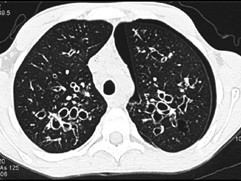

男,38岁,咳嗽、咳痰、咯血,结核菌素实验(-),结合CT图像,最可能的诊断是 ( ) WXJ-01891.jpg WXJ-01892.jpg

• D.支气管扩张